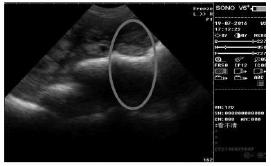

图1 妊娠18 d图像

②妊娠中期B超影像图表现及其特征

娠中期 (配种后 45 d~84 d) 是胎儿骨骼开始钙化到钙化完全的时期,由于羊水减少,孕囊变得不规则且不清晰 (见图 2),发育为胚胎,该时期的影像图上逐渐可见回声增强的白色强回声骨骼影像,80 d时,胎儿脊柱清晰显示。

图2 妊娠45 d图像